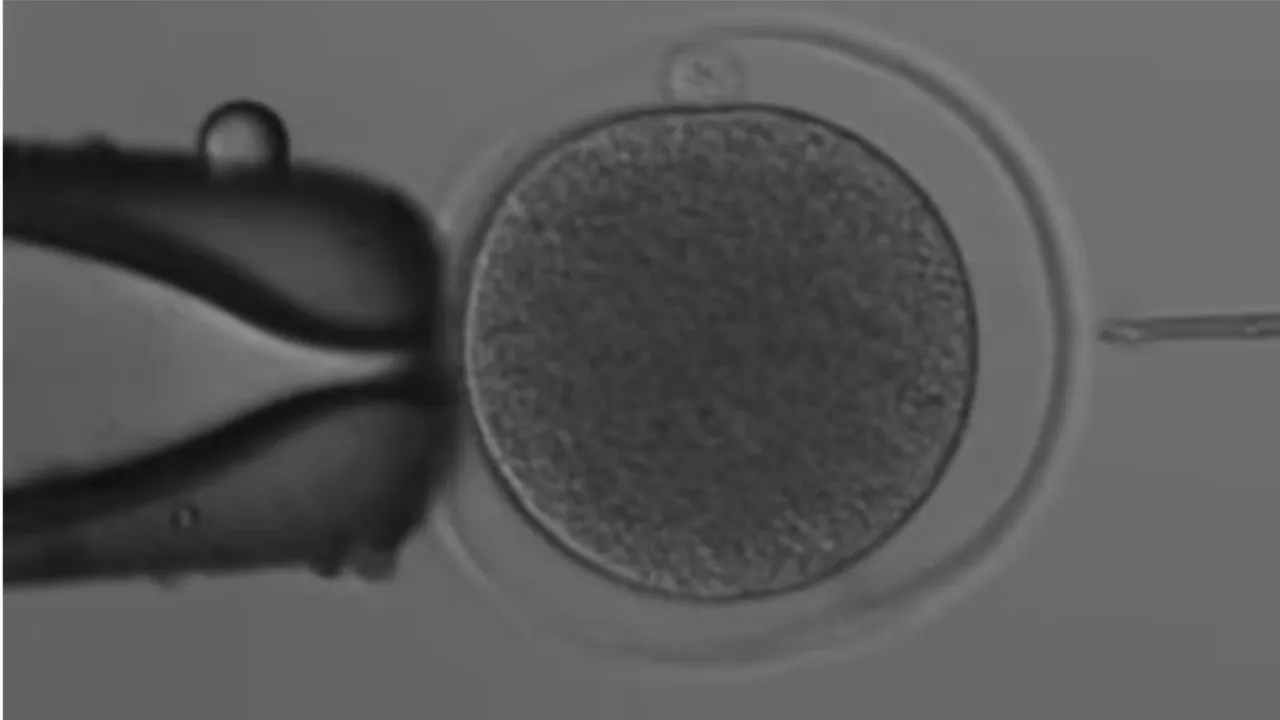

Embryos were then formed by the technique 'intracytoplasmic sperm injection (ICSI)', in which a sperm is directly injected into a mature egg.